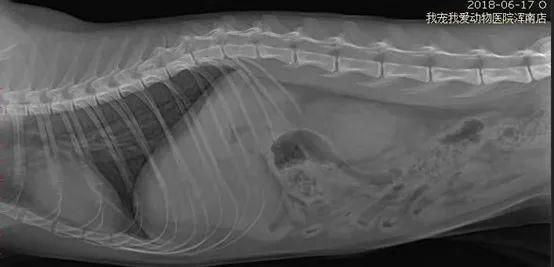

此外,对猫进行影像学猫腹腔右侧位DR和正位DR检查,通过综合分析,显示肠道小肠段均匀积气,最粗部位未大于第7腰椎直径。